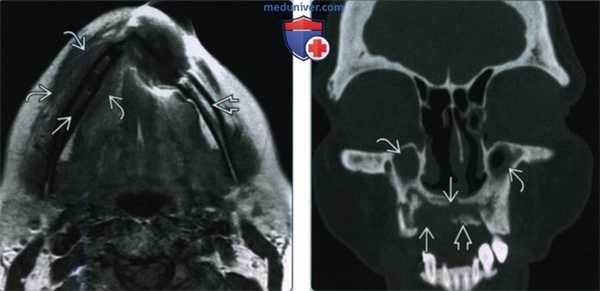

(Слева) На панорамной дентальной рентгенограмме у пациента, которому ранее было выполнено оперативное вмешательство и осуществлялась лучевая терапия полости рта, определяется диффузное утолщение и остеосклероз нижней челюсти, утолщение и деформация трабекул, нарушение дифференцировки кортикальной пластинки в области нижнего края нижней челюсти слева.

(Справа) При сагиттальной КТ (по углом) определяются множественные неоднородные «просветления» в кости, нарушение целостности кортикального слоя, утолщение и склероз трабекул и кортикальной пластинки. Обратите внимание на глубокую «лунку», оставшуюся после экстракции моляра. Определяется также фрагментация венечного отростка и шейки мыщелка.

(Слева) При аксиальной КТ с КУ определяется остеорадионекроз нижней челюсти справа, осложненный инфицированием жевательного пространства. Определяется также нарушение целостности кортикальной пластинки и диффузный, выраженный отек жевательных мышц и околоушной слюнной железы, расширение ее выводного протока, заполненного дебрисом воспалительного характера.

(Справа) При МРТ Т1ВИ в корональной проекции определяется диффузное замещение сигнала, в норме наблюдающегося в костном мозге, и характерного для жира. Пристствуют множественные участки нарушения целостности кортикальной пластинки. Индурация и отек подкожных тканей являются часто встречающимися изменениями при остерадионекрозе нижней челюсти.